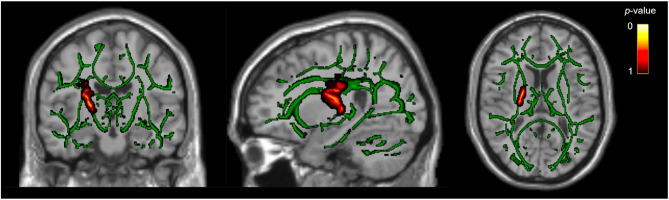

White matter tract differences in persistent post-traumatic headache, migraine, and healthy controls: a diffusion tensor imaging study.